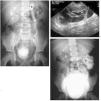

Objetivo: Ilustrar el espectro de hallazgos radiológicos de las duplicaciones del tracto urinario y mostrar la eficacia de los ultrasonidos, la cistouretrografía miccional seriada (CUMS), la urografía intravenosa (UIV), el estudio isotópico y la resonancia magnética (RM) en el manejo de estas entidades. Material y métodos: Hemos revisado retrospectivamente los hallazgos radiológicos de las duplicaciones del riñón, uréter, vejiga y uretra a partir de los datos de nuestro archivo de patología genitourinaria pediátrica. Todos los casos cuentan con estudio ecográfico, mientras que la CUMS, la UIV, el estudio isotópico y la RM se realizaron en función del tipo de duplicación. Hacemos hincapié en las bases embriológicas de los hallazgos radiológicos que, cuando fue posible, se cotejaron con los hallazgos anatomopatológicos. Resultados: Las duplicaciones completas o incompletas afectaron con más frecuencia al sistema pielocalicial y al uréter (pelvis renal bífida, uréter semibífido, uréter bífido bajo, duplicación ureteral completa y triplicación). Las duplicaciones vesicales se muestran en los planos sagital y coronal, aunque la forma más frecuente fue la división sagital con dos vejigas resultantes contiguas separadas por un pliegue peritoneal con tejido areolar fino. Las duplicaciones uretrales o las uretras accesorias se dieron fundamentalmente en el plano coronal; sin embargo, también describimos la duplicación en el plano sagital en ausencia de duplicación vesical. Mostramos un caso extremadamente raro de duplicación completa de uretra femenina. Conclusión: Mostramos una visión de conjunto de las duplicaciones del tracto urinario y discutimos la utilidad de varias técnicas de imagen disponibles. Dado que estas entidades tienen una apariencia radiológica característica, este artículo puede ser útil para comprender mejor estas anomalías.

Objective: To illustrate the spectrum of imaging findings for urinary tract duplications and to show the efficacy of ultrasonography (US), voiding cystourethrography (VCU), intravenous urography (IVU), scintigraphy, and magnetic resonance (MR) in the management of these entities. Material and methods: We have reviewed the imaging findings for cases of renal, ureteral, vesical, and/or urethral duplication from our pediatric genitourinary pathology archive. All patients underwent US examination; VCU, IVU, scintigraphy, and MR studies were performed in function of the type of duplication. We explain our findings within the framework of embryological development and correlate the imaging findings with the histopathologic findings whenever possible. Results: Complete or partial duplications most commonly affected the pyelocalyceal system or the ureters (bifid renal pelvis, bifid mid-ureter, low bifid ureter, complete ureteral duplication and triplication). Vesical duplications are shown in the sagittal and coronal planes, although the most common presentation was sagittal division resulting in two contiguous bladders separated by a peritoneal fold with thin areolar tissue. Ureteral duplication or accessory ureters were mostly seen in the coronal plane; however, we also describe duplication in the sagittal plane in the absence of vesical duplication. We show an extremely rare case of complete duplication of the female urethra. Conclusion: We provide an overview of the set of urinary tract duplications and discuss the usefulness of the different imaging techniques available for each type. As these entities have a typical radiological appearance, this article can help to understand these anomalies better.